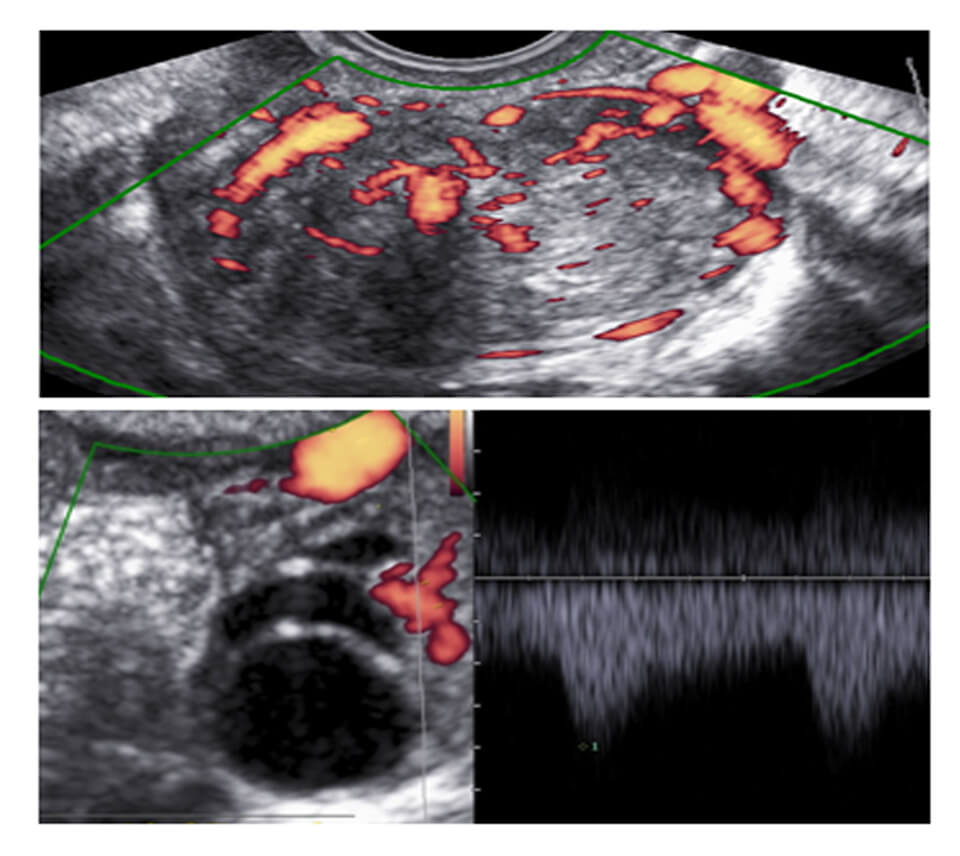

COLOR DOPPLER OBSTETRICS

SCHEDULE

Session 1 COLOR DOPPLER BASICS

KNOW YOUR MACHINE

Session 2 SHOW YOUR MACHINE

Session 3 DV/TR/UTERINE ARTERIES AT 11-14 WEEKS

Session 4 DV/UTERINE ARTERIES IN SECOND TRIMESTER + ASSIGNMENT SUBMISSION

Session 5 FETAL BIOMETRY APPROACH WITH MEASUREMENTS AND GRAPHS

Session 6 UMBILICAL/MCA/DV/AORTIC ISTHMUS + ASSIGNMENT SUBMISSION

Session 7 UMBILICAL/MCA/DV/AORTIC ISTHMUS + ASSIGNMENT SUBMISSION

Session 8 REVISION: START TO FINISH

REGISTRATIONS OPEN

WHY DO YOU NEED TO BE A PART OF THIS CLUB

1 MANY OF YOU HAVE A COLOR DOPPLER MACHINE OR PLANNING TO BUY ONE BUT ARE HESITANT WHETHER YOU WILL BE ABLE TO DO IT

2 THIS WAY YOU WILL BE ABLE TO KNOW AND LEARN FROM YOUR MISTAKES

3 THIS WILL COVER COLOR DOPPLER IN OBSTETRICS, GYNECOLOGY AND INFERTILITY

COLOR DOPPLER CLUB

Session 1 COLOR DOPPLER KNOBS AND SETTINGS

Session 2 COLOR DOPPLER ENDOMETRIUM (NORMAL AND ABNORMAL)

Session 3 COLOR DOPPLER MYOMETRIUM (NORMAL AND ABNORMAL)

Session 4 COLOR DOPPLER OVARIES (FOLLICLES,CYSTS,PCO,BENIGN VS MALIGNANT)

Session 5 COLOR DOPPLER EARLY PREGNANCY (NORMAL AND ABNORMAL)

Session 6 COLOR DOPPLER, 11-14 WEEKS (DV/TR/UTERINE)

Session 7 UTERINE ARTERIES : SECOND AND THIRD TRIMESTER

Session 8 COLOR DOPPLER SECOND TRIMESTER ANOMALIES AND CARDIAC EVALUATION

Session 9 FETAL ANEMIA/TWINS/ACCRETA

Session 10 FETAL BIOMETRY

Session 11 COLOR DOPPLER THIRD TRIMESTER : DECIDING MANAGEMENT, FOLLOLW UP AND TERMINATION

Session 12 COLOR DOPPLER BASICS

KNOW YOUR AND MY MACHINE

CDC : INFERTILITY

BASELINE SCAN

ENDOMETRIAL FLOW OVARIAN STROMAL FLOW

FOLLICLE MONITORING

ENDOMETRIAL ZONAL VASCULARITY UTERINE ARTERY DOPPLER PERI-FOLLICULAR VASCULARISATION FOLLICLE PSV

LUTEAL PHASE

CORPUS LUTEAL FLOW

CDC : GYNECOLOGY

CDC : PREGNENCY (04-14)

04-10 WEEKS

CORPUS LUTEUM

RPOC

MISSED

MOLAR

11-14 WEEKS

FDV

TR

UTERINE ARTERIES